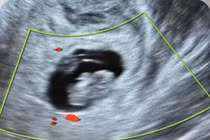

Bệnh nhân L.P.A (40 tuổi, Hải Dương) nhập viện trong tình trạng đau bụng kéo dài suốt 2 tuần nhưng chưa xác định được nguyên nhân. Điều đáng chú ý là dù đã xét nghiệm máu cho kết quả có thai, song nhiều lần siêu âm (kể cả siêu âm đầu dò) tại một số cơ sở y tế, đều không phát hiện hình ảnh túi thai trong tử cung hay phần phụ. Chính vì vậy, đã đặt ra một nghi ngờ lớn về vị trí làm tổ bất thường của khối thai.

Một ngày trước khi vào viện, cơn đau bụng của bệnh nhân đột ngột tăng dữ dội, lan xuống vùng hạ vị và thắt lưng. Trước diễn biến bất thường, các bác sĩ đã mở rộng hướng tiếp cận, chỉ định siêu âm ổ bụng và phát hiện một khối chửa kích thước lớn, kèm theo khối máu cục xung quanh.

Tuy nhiên, điều khiến ê-kíp đặc biệt lo ngại không chỉ là kích thước hay lượng máu tụ, mà chính là khối chửa nằm ở vị trí cực kỳ nguy hiểm, ngay phía trước tĩnh mạch chủ bụng (một trong những mạch máu lớn của cơ thể), nếu xảy ra tổn thương, nguy cơ mất máu ồ ạt và tử vong là rất cao.